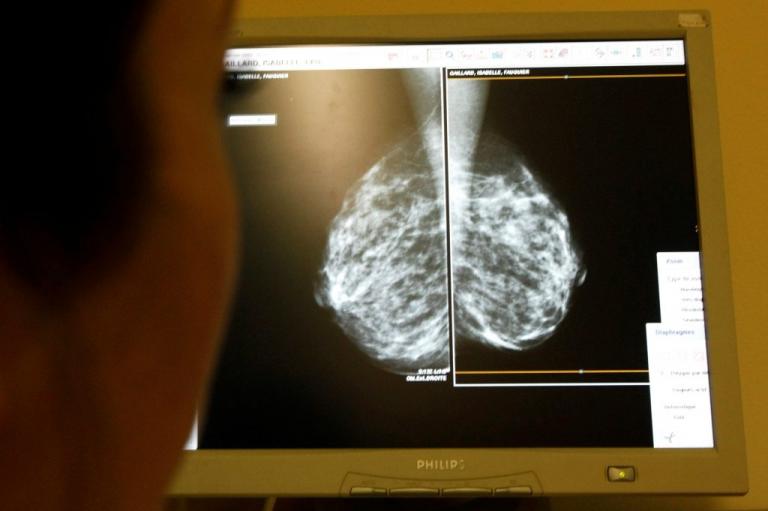

Ένα "λάθος" φαίνεται να έχει κοστίσει την ζωή σε πολλές γυναίκες στην Βρετανία. Σύμφωνα με το BBC, 450.000 γυναίκες ηλικίας από 50 έως 70 ετών δεν πήραν ποτέ πρόσκληση από το βρετανικό εθνικό σύστημα υγείας για να κάνουν μαστογραφία.

Από τις 450.000 γυναίκες που δεν κλήθηκαν, οι 300.000 έχουν κλείσει τα 70 τους χρόνια. Σύμφωνα με όσα μεταδίδει το BBC, το «λάθος» έγινε μετά το 2009 και ήρθε στο φως τον περασμένο Ιανουάριο. Όλες οι γυναίκες που επηρεάζονται άμεσα από το συγκεκριμένο «λάθος» έχουν περάσει τα 70 τους χρόνια και αναμένεται να κάνει δήλωση ο υπουργός Υγείας.

Το σύστημα υγείας στην Βρετανία προβλέπει την αποστολή πρόσκλησης για μαστογραφία σε γυναίκες ηλικίας από 50 έως 70 ετών. Η πρόσκληση αποστέλλεται κάθε τρία χρόνια. Κι αυτό, γιατί η πιθανότητα να εμφανίσουν καρκίνο του μαστού αυξάνεται όσο περνούν τα χρόνια. Για το «λάθος» «καταδικάστηκαν» οι ηλεκτρονικοί υπολογιστές αλλά οι κακές γλώσσες λένε ότι μάλλον κάποιοι έβαλαν το χεράκι τους ώστε όσες από αυτές τις γυναίκες μπορούσαν να απευθυνθούν στον ιδιωτικό τομέα…